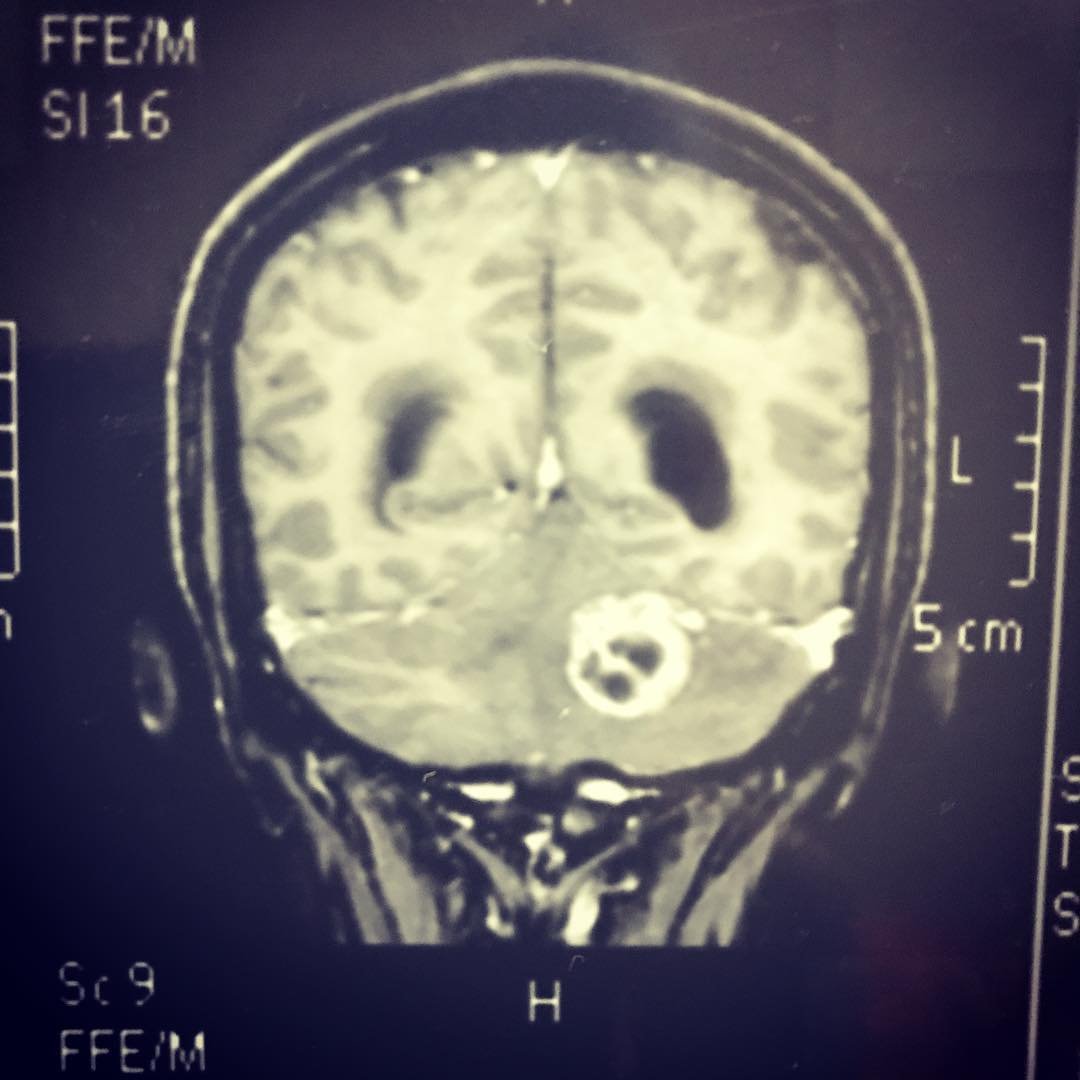

Cirugía para hidrocefalia